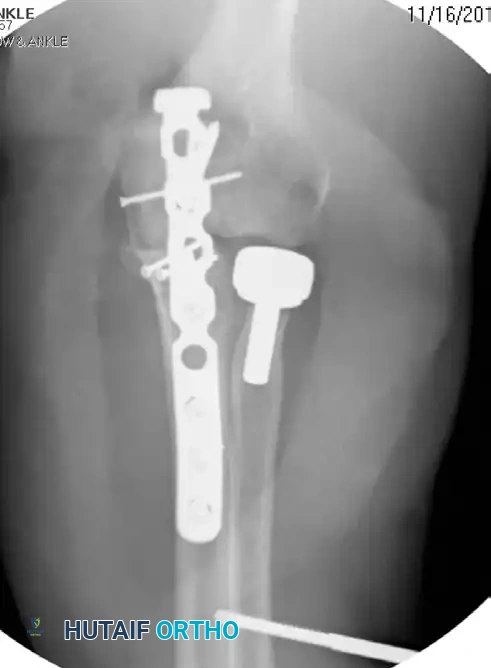

Complex Olecranon Fracture-Dislocation (Injury):

Fixation with Low-Profile Plate (AP View):

Fixation with Low-Profile Plate (Lateral View):

These injuries vary in complexity, often presenting with extensive comminution and coronoid involvement. The routine treatment protocol demands anatomical reconstruction of the greater sigmoid notch articular surface followed by rigid plate fixation. The coronoid must be reduced and stabilized with lag screws first, followed by provisional articular reduction, and finally, a robust plate spanning the entire zone of injury.

Preoperative Transolecranon Fracture-Dislocation:

Fixation with Lag Screws and Plate Spanning Entire Injury (AP View):

Fixation with Lag Screws and Plate Spanning Entire Injury (Lateral View):

Fixation with Lag Screws and Plate Spanning Entire Injury (Oblique View):